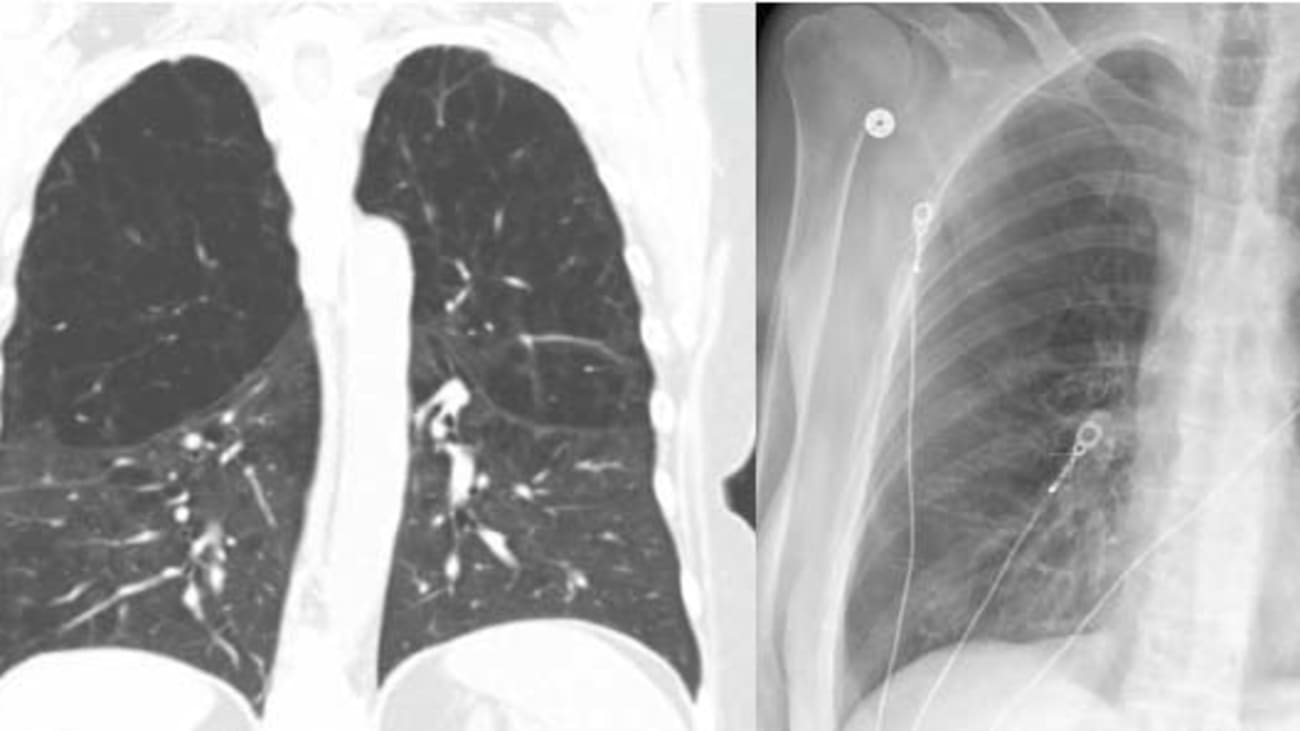

Bronchoscopic Lung Volume Reduction Using Endobronchial Valves Imaging Valves In Copd 1,2 bronchoscopic placement of ebvs in a suitable target lobe, with proven absence of collateral ventilation with the u. They prevent air from entering the most damaged areas while allowing air that’s. Lung valves help control the flow of air in lungs that have been damaged by emphysema. And during inhalation, the valves close. During exhalation, the valves open, allowing. Valves In Copd.

Bronchoscopic Lung Volume Reduction Using Endobronchial Valves Imaging Valves In Copd During exhalation, the valves open, allowing air and other secretions to escape from the treated lobe. For patients with severe copd or emphysema, a new treatment option known as the zephyr® endobrachial valve system has proved. Endobronchial valve (ebv) treatment for emphysema, summary of treatment selection and outcome. To date, the benefits have been. They prevent air from entering the. Valves In Copd.